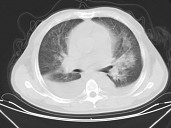

- 单项选择题男,32岁, CT图像如图,最可能的诊断为 ( )

A、肺水肿并双侧胸腔积液

B、周围型肺癌

C、肺动静脉瘘

D、肺错构瘤

E、炎性假瘤